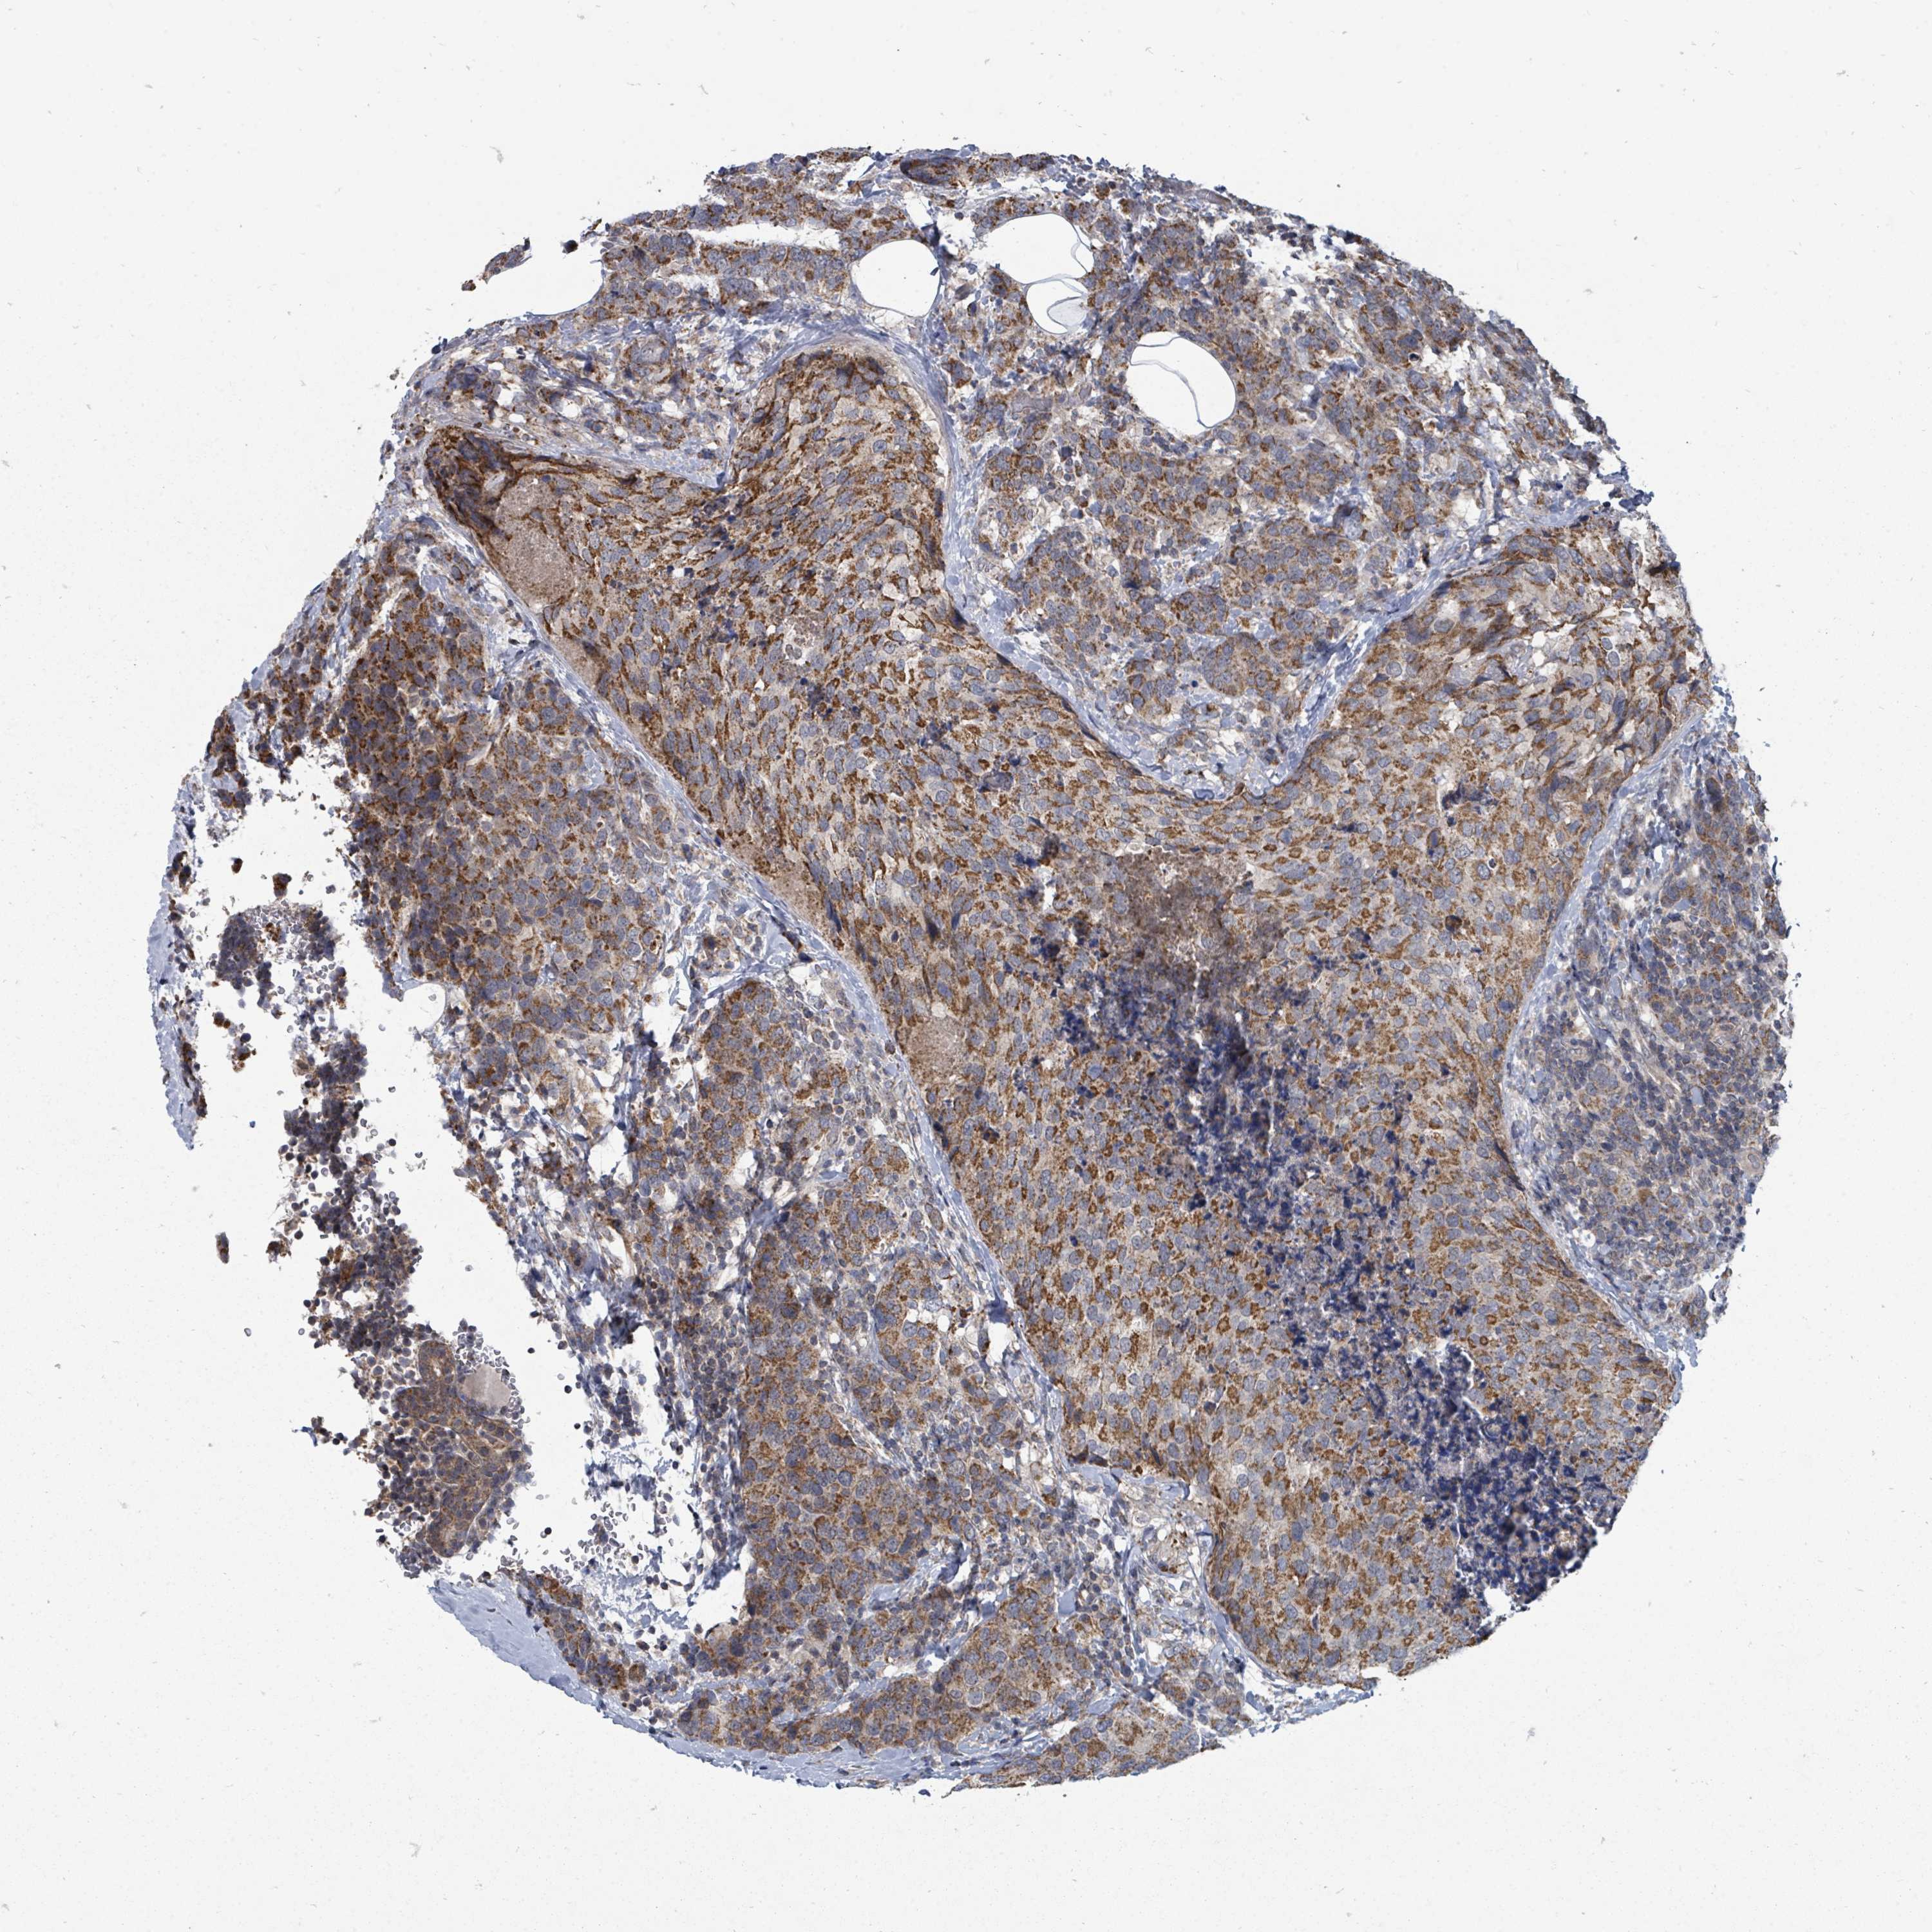

CANCER BREAST CANCER Show tissue menu

BRCA TCGA BRCA VALIDATION PROTEIN EXPRESSION